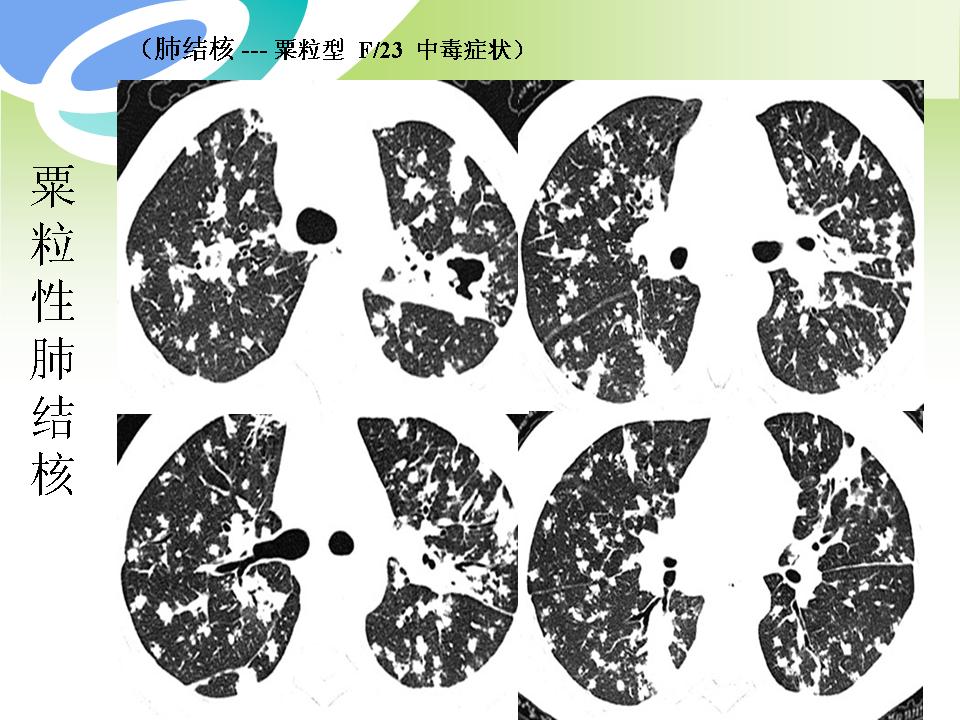

肺部病变的CT基本征象